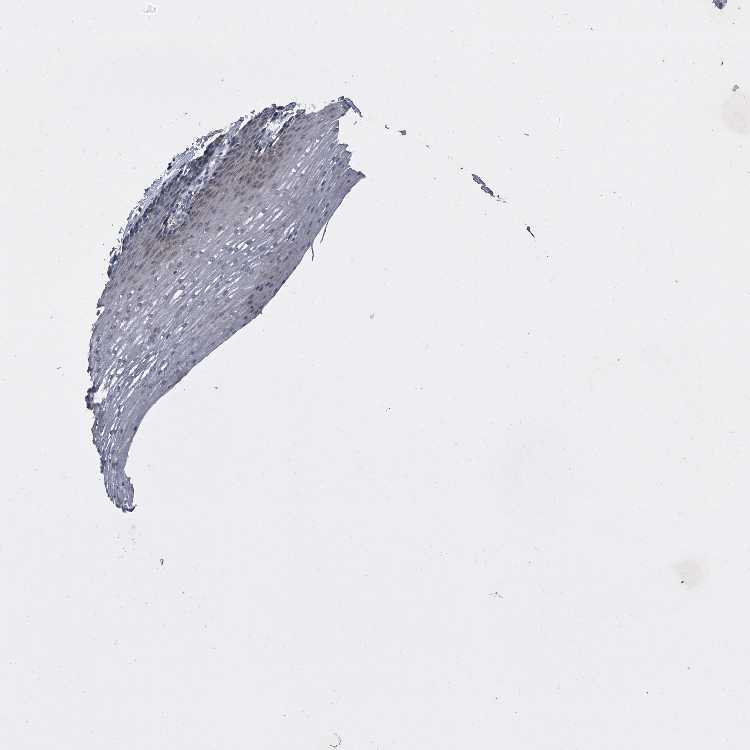

ESOPHAGUS - Antibody stainingi

Antibody staining in the annotated cell types in the current human tissue is reported as not detected, low, medium, or high, based on conventional immunohistochemistry profiling in selected tissues. This score is based on the combination of the staining intensity and fraction of stained cells.

Each image is clickable and will lead to virtual microscopy that enables deeper exploration of all samples and also displays staining intensity scores, fraction scores and subcellular localization as well as patient and tissue information for each sample.

Antibody HPA029137Antibody HPA029138Antibody HPA029139

Squamous epithelial cells HighMediumLow